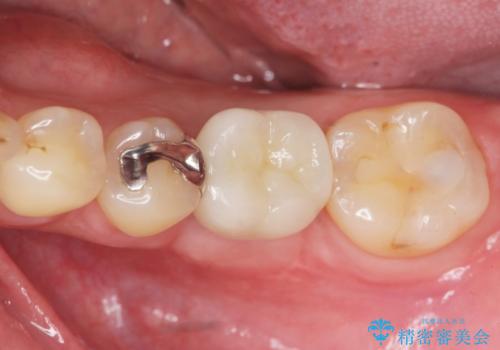

- 銀歯が揺れる、噛むと痛い、と治療を希望され来院されました。

銀歯・レジンコアを除去したところ、薄い残存歯質に亀裂が入り、保存が難しい状況が認められました。